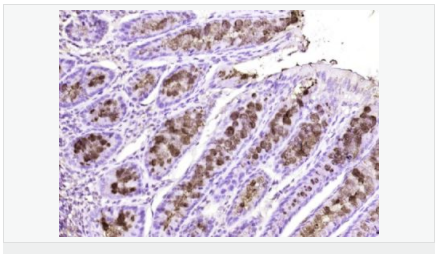

| 產(chǎn)品應用 | ELISA=1:5000-10000 IHC-P=1:100-500 IHC-F=1:100-500 IF=1:100-500 (石蠟切片需做抗原修復) not yet tested in other applications. optimal dilutions/concentrations should be determined by the end user. |

| 產(chǎn)品介紹 | Fc (Ig constant fragment) receptors ensure protection of the host against foreign antigens, such as microorganisms and pathogens, by removing Ig-coated antigen complexes from circulation. Fc receptors are present on lymphoid and myeloid derivatives, where they mediate endocytosis of Ig-antigen complexes, antibody production in B cells through T cell antigen presentation, cytotoxicity and the release of cytokines and reactive oxygen species. The Fc γ-binding protein (FCGBP) interacts with the Fc portion of IgG and MUC2 to mediate the maintenance of the mucosal structure. FCGBP is a 5,405 amino acid protein that contains twelve TIL (trypsin inhibitory-like) domains and thirteen VWFD domains. It is predominantly expressed in placenta and colon epithelium as well as in thyroid and serum. Patients with various autoimmune diseases seemingly have higher levels of FCGBP protein present in their serum. Function: May be involved in the maintenance of the mucosal structure as a gel-like component of the mucosa. Subunit: Interacts with the Fc portion of IgG and with MUC2. Subcellular Location: Secreted. Tissue Specificity: Mainly expressed in placenta and colon epithelium. Expressed in thyroid, and down-regulated in thyroid carcinomas. Present in serum, with higher levels in patients with various autoimmune diseases (at protein level). Similarity: Contains 12 TIL (trypsin inhibitory-like) domains. Contains 13 VWFD domains. SWISS: Q9Y6R7 Gene ID: 8857 Database links: Entrez Gene: 8857 Human SwissProt: Q9Y6R7 Human Unigene: 111732 Human Important Note: This product as supplied is intended for research use only, not for use in human, therapeutic or diagnostic applications. |